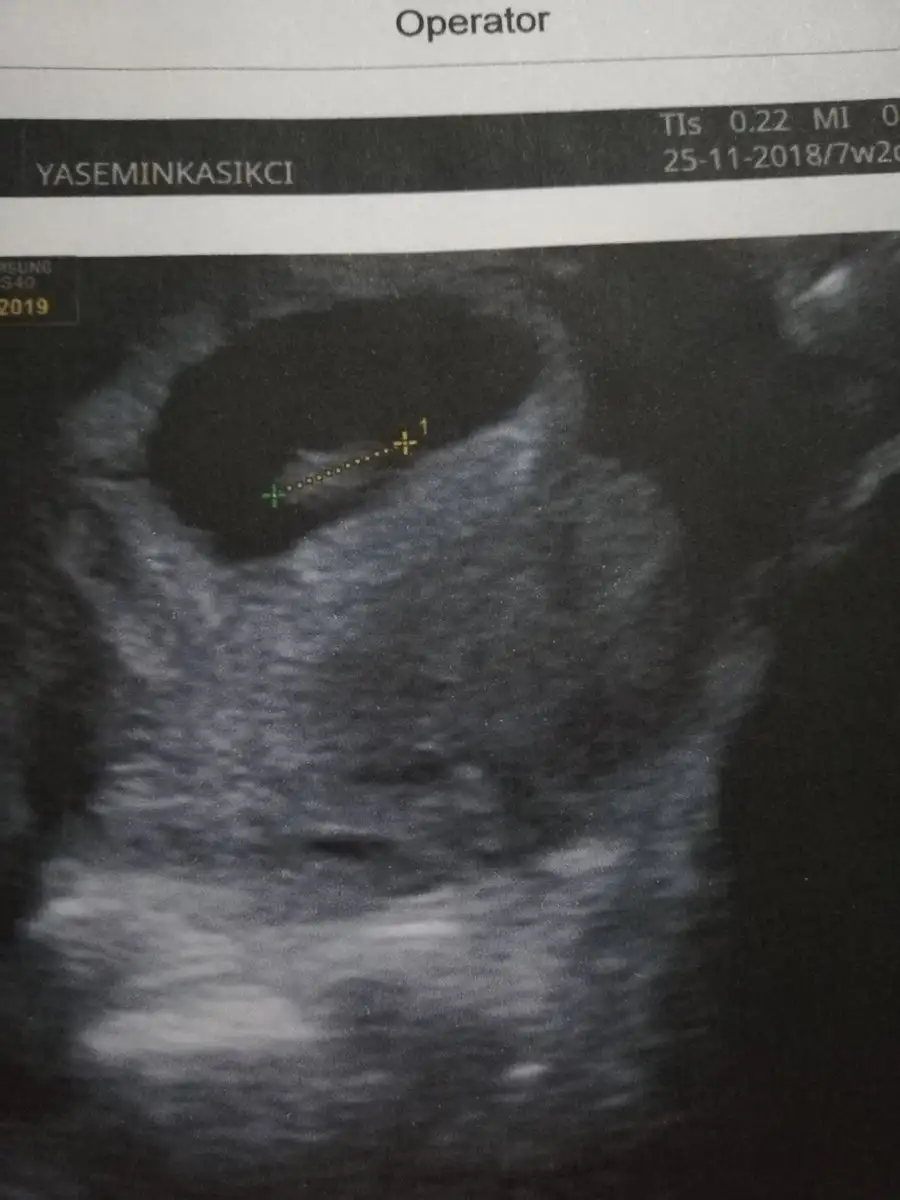

Ypk kuzum aynı foto işte. Karından. Arkadaş öyle diyince buraya da atayım dedim. Bildiğin solda bebek. Kızımın usg sine bakıyorum oda en sağa yapışık. Tam tersi tarafta. Senin usg yi atsana bi 7 haftalık olanı

Çok teşekkür ederim Rabbim gonlunuzden geçeni kabul etsin USG görüntümüz karındanGözün aydın :) kese konumuna göre sağ da mıydı solda mı ? Benim kızım sağdaydı. Bu gebelikte solda. Kızlar Buda kız dedi ama ben erkek hissediyorum![]()

Bak aynı doktor aynı makine bu da kızım 7+2 :) demek istediğim bu

Senin kızlar tersi tarafta mıydı karşılaştırdın mıBak canım benimki solda, senin bebek sağda duruyor

Nuba göre bakılmıştı onda . Kese bu 7 haftalık